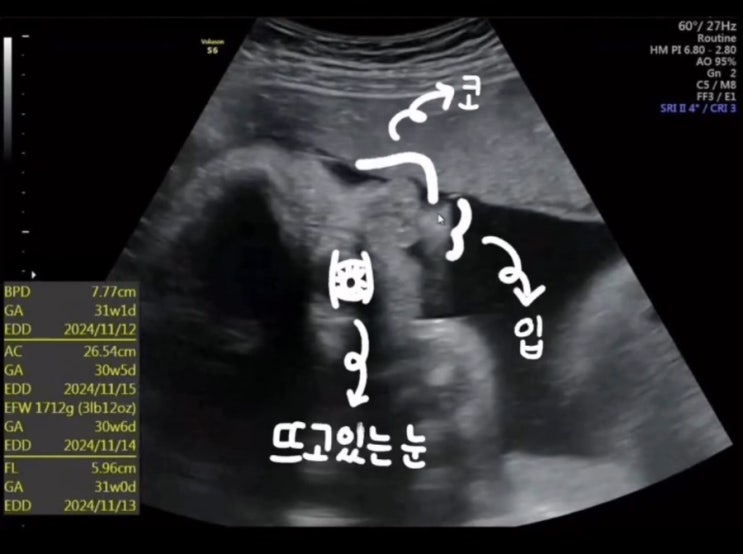

13. 대구 수성구 효성병원(#13. 32주 3일 정기검진)

12. 대구 수성구 효성병원(#12. 30주 2일 태동검사 및 백일해 주사 접종)

포스팅 시작하기에 앞서... 마지막포스팅이 9월이였네요! ㅜ.ㅜ 출산 하면 겨울생 아기라 한동안은 밖에 나...